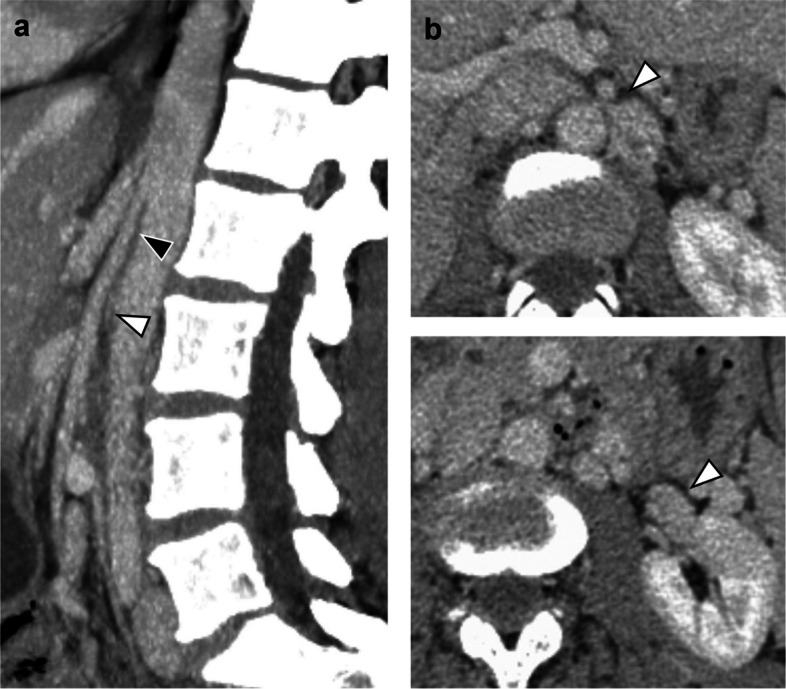

The optimal management strategy of nutcracker syndrome is debated, especially in the setting of concurrent pelvic congestion syndrome. In this article, we describe our treatment algorithm as illustrated by four different case scenarios. In our experience, renocaval pressure gradients are often inconclusive, but evaluation of the left renal vein waveform as well as a "test PTA" with evidence of a waist in the balloon can be helpful in unmasking a relevant stenosis. We consider nutcracker syndrome not to be a contraindication for ovarian vein embolization. Decision for simultaneous or sequential stenting should be based on angiographic findings and clinical course.